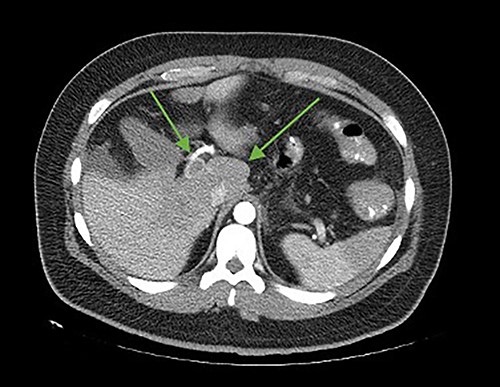

The patient was reoperated by laparoscopy, finding segmental thrombosis from 200 cm to 50 cm of the Treitz ligament, with edema and interloop free fluid without perforation (Figs 3 and 4). Lateral resection and entero–entero anastomosis were performed with manual stapler, subtracting 440 cm of intestine with adequate coloration. Later he was admitted to the Intensive Care Unit, treated with low molecular weight heparin at a full anticoagulation dose, maintaining an INR of 2 and a partial thromboplastin time of 80 s. He presented adequate evolution starting a liquid diet on the fourth postoperative day, new laboratories reported hemoglobin of 11 g/dl, 12 700 leukocytes/mm3, platelets 225 000/mcL, INR of 2. He was discharged on the fifth day with rivaroxaban treatment for 6 months.

Laparoscopic view of intestinal thrombosis 200 cm at the level of the proximal jejunum, 50 cm from the ligament of Treitz.